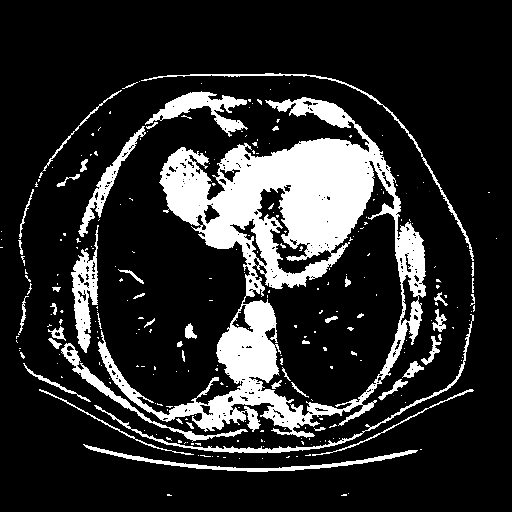

Reconstructed NATIVE CT scan (cycle consistency)

Full window (WL 1023.5, WW 4095 β†’ Low βˆ’1024, High +3071)

Actual HU range: [-1024.0, 3071.0]